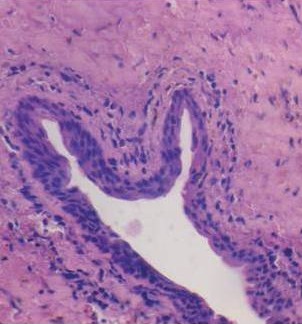

EXTRAORAL PICTURE RADIOGRAPHIC APPEARANCE HISTOPATHOLOGICAL PICTURE

RADIOGRAPHIC APPEARANCE HISTOPATHOLOGICAL PICTURE

INTRAORAL PICTURE CBCT APPEARANCE HISTOPATHOLOGICAL PICTURE

HAEMATOXYLIN-EOSIN STAIN PICROSIRIUS RED STAIN POLARIZATION MICROSCOPE